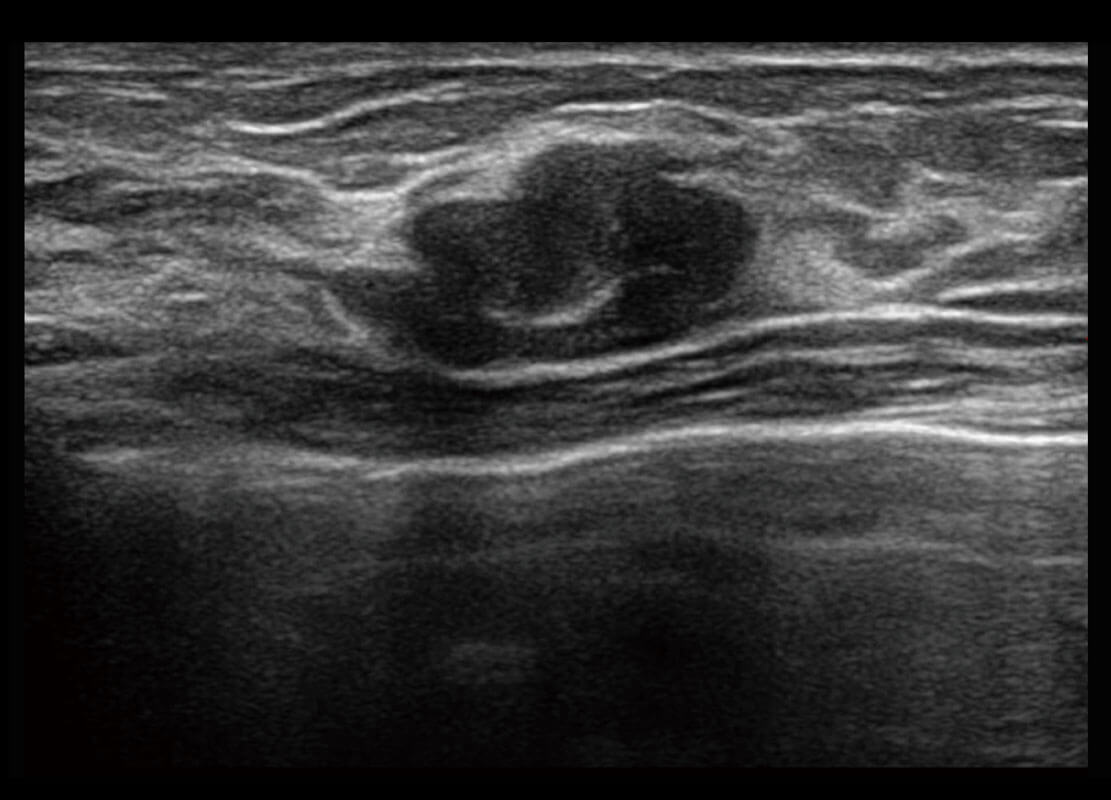

P60搭載寬頻帶線(xiàn)陣探頭、寬景成像、彈性成像技術(shù),為您提供乳腺應(yīng)用方案。P60支持高頻相控陣探頭、線(xiàn)陣探頭、腹部高頻探頭、腹部微凸探頭等,豐富的探頭群搭載敏感的彩色血流成像,適用于新生兒多種臟器檢測(cè)要求,滿(mǎn)足新生兒篩查需求。

乳腺導(dǎo)管癌

乳腺癌顯微血流